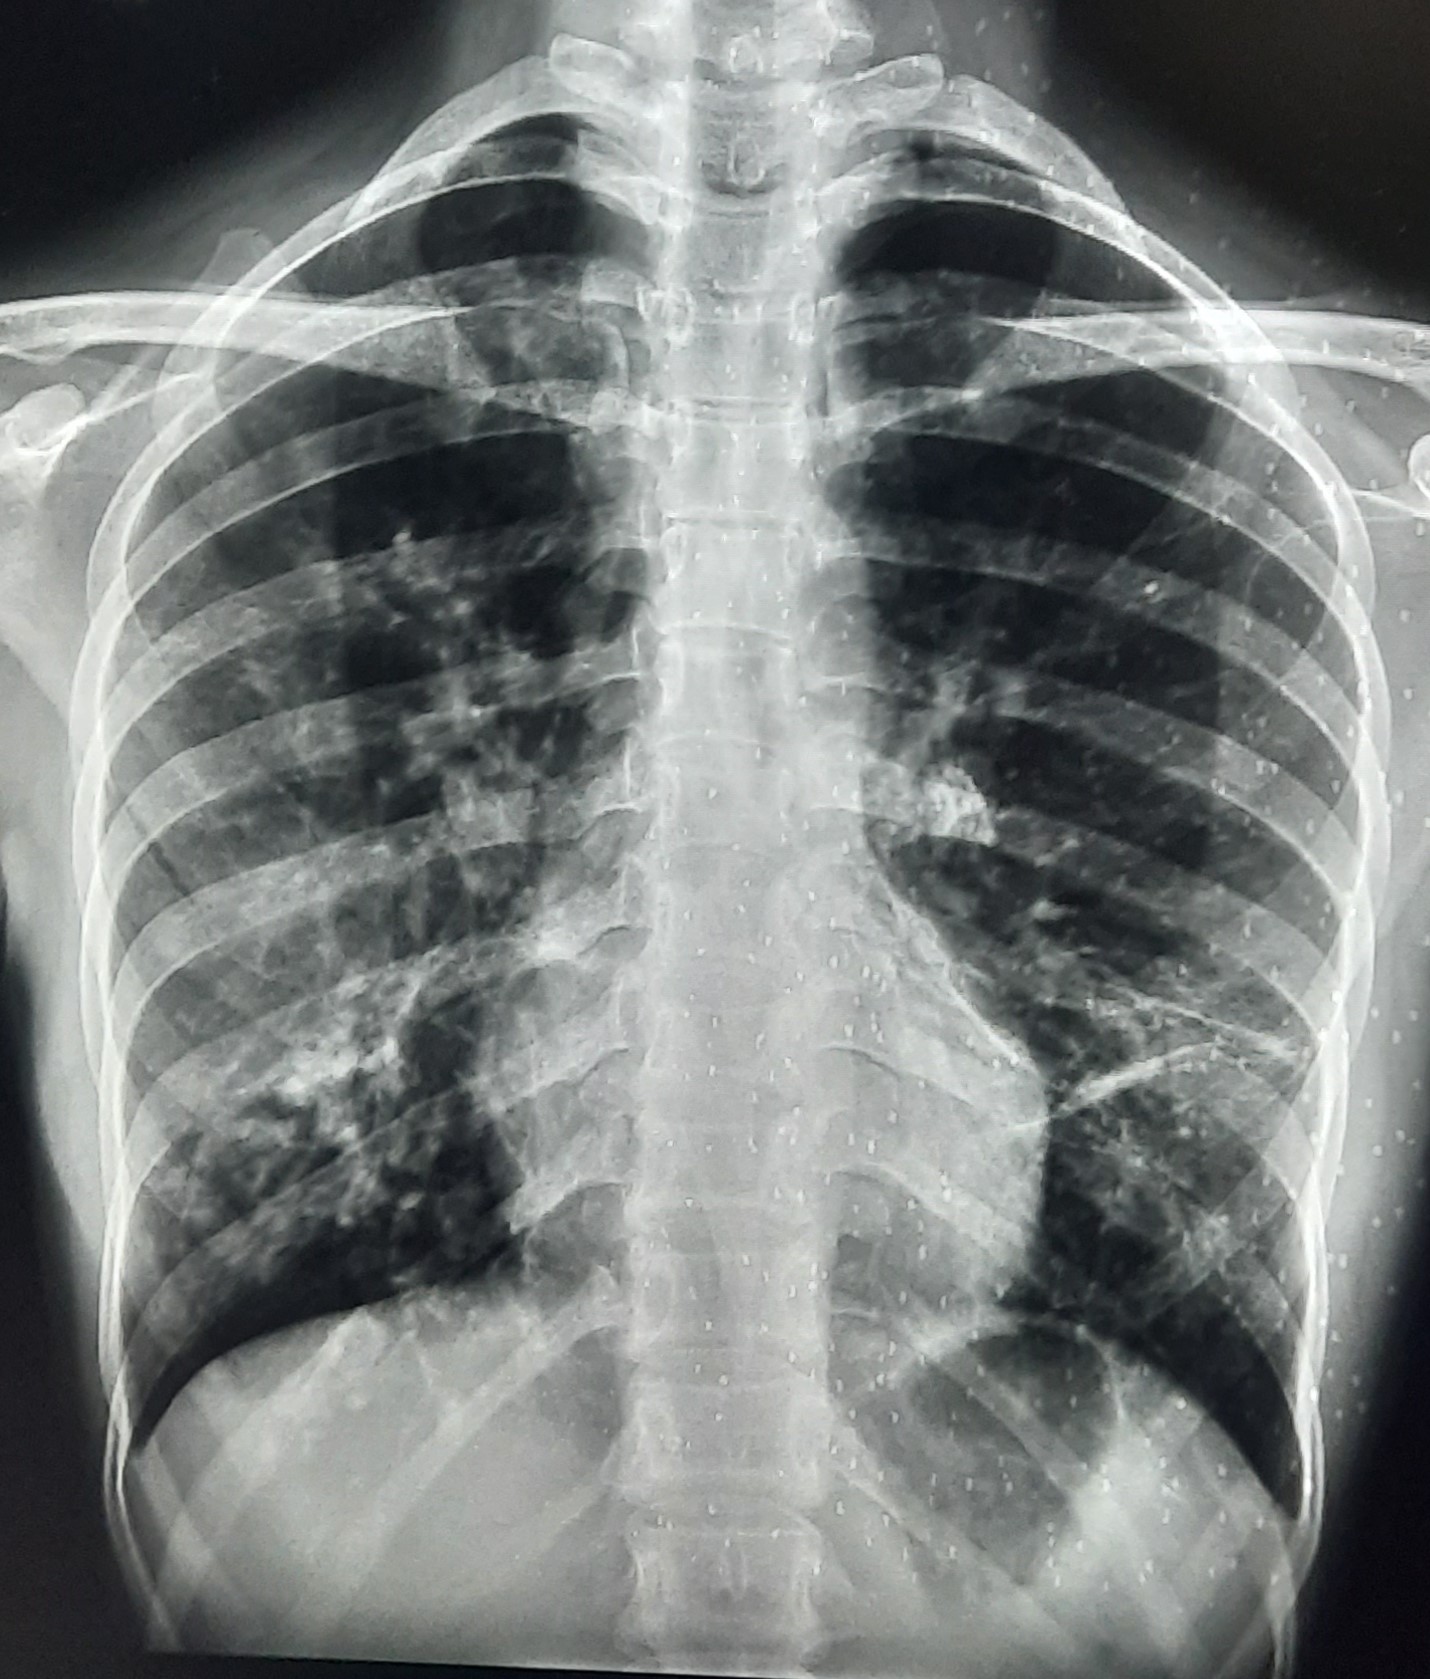

| 251 | IGGMC, Nagpur, Nagpur | P2 | 29-4221 | Ganpat Gaikawad | Consent taken on Paper | 70 Yrs. |

Provisional Diag : post TB sequele?

Final Diag : Fibrosis |

Non-TB Case (Confirmed) | Fibrosis | Abnormality visible on x-ray |